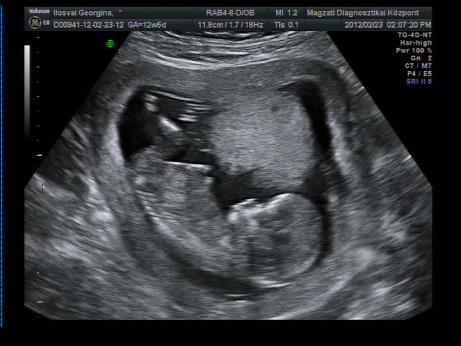

Igigig: de marha jó ez az uh kép!! tök jól látszik a kis pofija!

Úgy néz ki, hogy kislány, 99,5 % Lehetett látni a szemérem ajkakat. Egyszer volt hajlandó kicsit megfordulni. Semmi kóros nem látható.